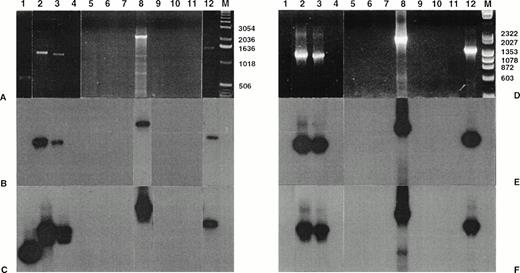

After standard DNA-PCR, 4 of the 11 cases with a chimeric transcript detected by nested RT-PCR showed a specific amplicon (Fig 4). The size of the chimeric amplicons varied from case to case, ranging between 0.8 and 2.9 kb, according to variable intronic breakpoints.23,40 These cases, which were previously found to contain NPM-ALK transcripts by standard RT-PCR, corresponded to 3 CD30+ secondary CTCL (cases no. 1, 2, and 3) and 1 CD30+ primary CTCL (case no. 8). The nested amplification allowed the detection of size-specific amplicons in the same cases (no. 1, 2, 3, and 8) and in 2 additional CD30+primary CTCL (cases no. 7 and 9). Titration experiments showed that the sensitivity of DNA-PCR was 10−3 for the standard PCR and 10−4 for the nested PCR (data not shown). Southern blot hybridization of PCR products confirmed the specificity of these results, giving a positive signal with both NPM-5P and ALK-5P in the 3 CD30+ secondary CTCL and in one CD30+primary CTCL (case no. 8). However, the 2 other CD30+primary CTCL with a visible amplicon after nested DNA-PCR (cases no. 7 and 9) hybridized only with ALK-5P but not with NPM-5P. Moreover, 1 case of LyP (case no. 4) was shown to give a positive hybridization only with ALK-5P, although no signal was detectable on ethidium bromide-stained gel. The nested DNA-PCR amplicon of case no. 7 was sequenced and found to contain the 3′ end of the ALK exon targeted by the 3′ALKint oligonucleotide and the flanking intron, but lacked the 5′ end of the NPM exon targeted by the 5′NPMint oligonucleotide. In cases no. 4 and 9, the amount of amplicon was too low to perform sequencing. Size-specific amplicons of cases no. 1, 2, 3, and 8 were sequenced and shown to contain chimeric intronic sequences between the flanking 5′NPM and 3′ALK exons. Multiple alignment analysis of these sequences with the t(2;5) genomic nucleotide sequence of SU-DHL-122 showed a perfect homology of the ranging from both exonic extremities over a variable intronic area from case to case depending on the location of the breakpoint (data not shown). In contrast, all MF and BID cases were negative even after nested DNA-PCR.

Amplification of genomic breakpoint on derivative chromosome 5. Genomic DNA was subjected to standard and nested amplification, followed by product separation on a 1% agarose gel. Ethidium bromide staining of standard DNA-PCR products (A) and of nested DNA-PCR products (D). Lanes 1 through 11, cases no. 1 through 11; lane 12, t(2;5)+ SU-DHL-1 cell line; lane M, molecular weight marker 1-kb DNA ladder (GIBCO-BRL). The gels were transferred to a nylon membrane and hybridized either with the ALK-5P (radioautographies B and E) or the NPM-5P (radioautographies C and F). The sizes are indicated in bases.

Amplification of genomic breakpoint on derivative chromosome 5. Genomic DNA was subjected to standard and nested amplification, followed by product separation on a 1% agarose gel. Ethidium bromide staining of standard DNA-PCR products (A) and of nested DNA-PCR products (D). Lanes 1 through 11, cases no. 1 through 11; lane 12, t(2;5)+ SU-DHL-1 cell line; lane M, molecular weight marker 1-kb DNA ladder (GIBCO-BRL). The gels were transferred to a nylon membrane and hybridized either with the ALK-5P (radioautographies B and E) or the NPM-5P (radioautographies C and F). The sizes are indicated in bases.